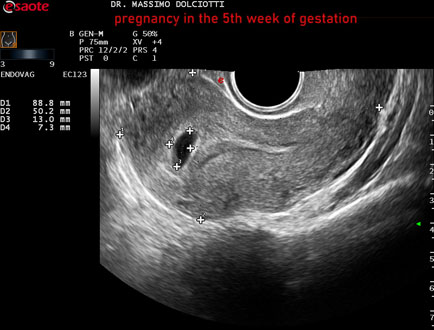

Data inserimento: 12/12/2025

Ecografia del: 31/11/2025

Strumento: Esaote MyLab Eight

Sonda: Convex Multifrequenza 1-8 MHz ed Endocavitaria Multifrequenza 3-9 MHz

Età Paziente: F 28 anni

Motivazione dell'esame: amenorrea e BETAHCG POSITIVO 17 mila.

Commento all'esame: le immagini ed il video documentano la camera gestazionale delle dimensioni di 13 x 7 mm e presenza di sacco vitellino delle dimensioni di 3,3 mm.

Conclusioni: gravidanza alla quinta settimana di gestazione (pregnancy in the 5th week of gestation).

Presentazione: Dr. Massimo Dolciotti - Ancona

Elaborazione digitale: Andrea Dini - Ancona